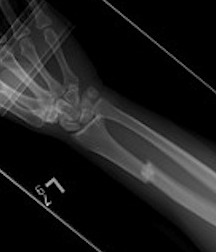

Shortening of radius with disruption of DRUJ on lateral

Concern for disruption of DRUJ on lateral

1. Anatomical ORIF of distal radius with dynamic compression plate

- anatomical reduction

- restoration of radial bow

- compression for healing

Radius ORIF with dynamic compression plates